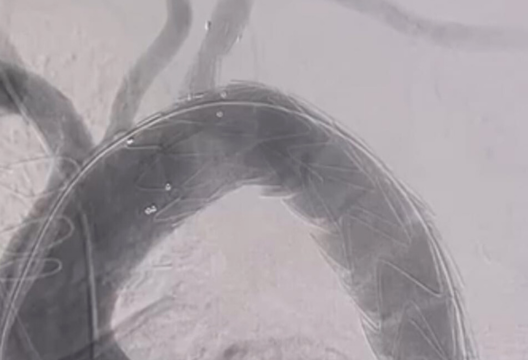

Алайда, тиімді және қауіпсіз шешім бар және әлемнің көптеген клиникаларында белсенді түрде жүзеге асырылуда. UMC Жүрек Орталығының мамандары озық тенденцияларға сүйене отырып, ТМД және Орта Азия елдері арасында алғаш рет Castor графтінің аз инвазивті имплантациясының жаңа технологиясын қолданды. Бұл стент-графт арнайы полимермен қапталған және әлсіреген қолқа қабырғасын нығайтатын металл жақтаудан тұрады. Стендтің бірегейлігі оның құрылымында, онда дене аорта және созылған бүйір тармақ имплантация кезінде бір-біріне тігіліп, ашылады. Стент пен оның тармағының позициясы жоғарғы аяқтың қанмен қамтамасыз етілуін бұзбау үшін пациенттің анатомиялық ерекшеліктеріне сәйкес бекітіледі және бейімделеді.

Стент-графт имплантациялау процедурасы сан артериясындағы пункция арқылы катетерді енгізіп, жалпы анестезиямен аз инвазивті түрде орындалды. Пациент өзін жақсы сезініп шығарылды. Шеберлік сабаққа Алматы және Семей клиникаларының дәрігерлері де қатысты. Жаңа стент-графтты енгізу елордада да, өңірлерде де пациенттер үшін емдеу сапасын және үздік медициналық тәжірибелердің қолжетімділігін жақсартуға мүмкіндік береді.